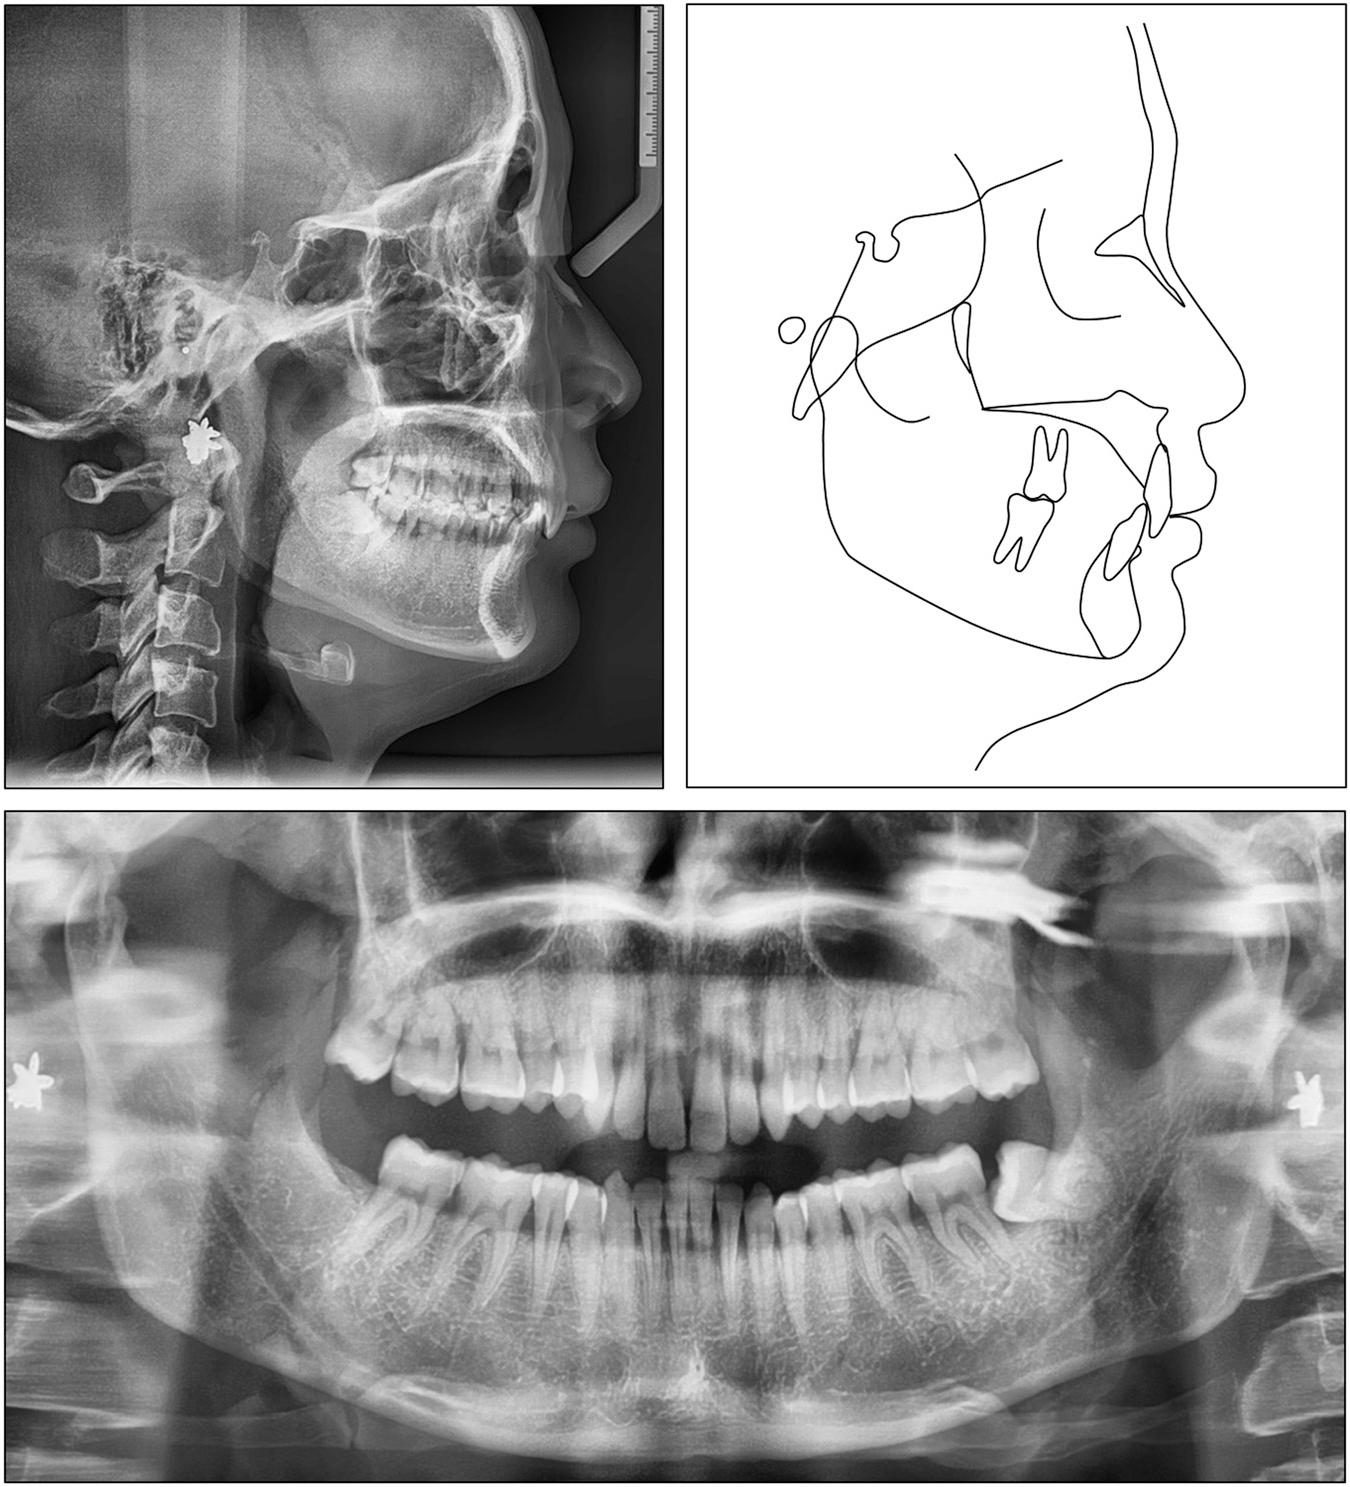

Figure 1.